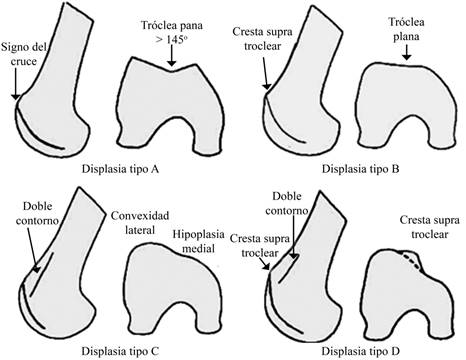

La displasia troclear se define como un surco troclear con un ángulo mayor de 145o.2,3 La misma se evalúa combinando una serie de cortes tomográficos axiales de la tróclea femoral y mediante un perfil estricto de rodilla (existiendo una perfecta superposición de ambos cóndilos femorales en su región posterior). En la radiografía simple se valorará el contorno de las facetas y posterior a ellas, la línea que representa la parte más profunda del surco troclear.

En las proyecciones de perfil, la displasia troclear se define como el «signo del cruce» de Dejour, donde la línea radiográfica de la tróclea cruza o se superpone a la proyección de ambos cóndilos femorales. El «signo de cruce» representa la ubicación exacta en la que el punto más profundo de la tróclea femoral alcanza la misma altura que la de los cóndilos femorales, lo que significa que la tróclea se hace plana o incluso hasta convexa (representada con una saliente) en esta ubicación exacta (Figura 4).

Por otro lado, la imagen del doble contorno representa la hipoplasia de la faceta medial, siendo posterior y menor que la faceta lateral en esta proyección. Con estos criterios y utilizando los cortes tomográficos axiales, se puede clasificar la displasia troclear en cuatro tipos (Figura 5): tipo A (la tróclea es menos profunda que lo normal, pero simétrica y cóncava. Presenta el signo de cruce), tipo B (la tróclea es plana o convexa. Presenta una saliente troclear), tipo C (signo del doble contorno en la proyección lateral de la radiografía simple. La faceta lateral es convexa en la tomografía axial) y tipo D (combina todos los signos anteriores).